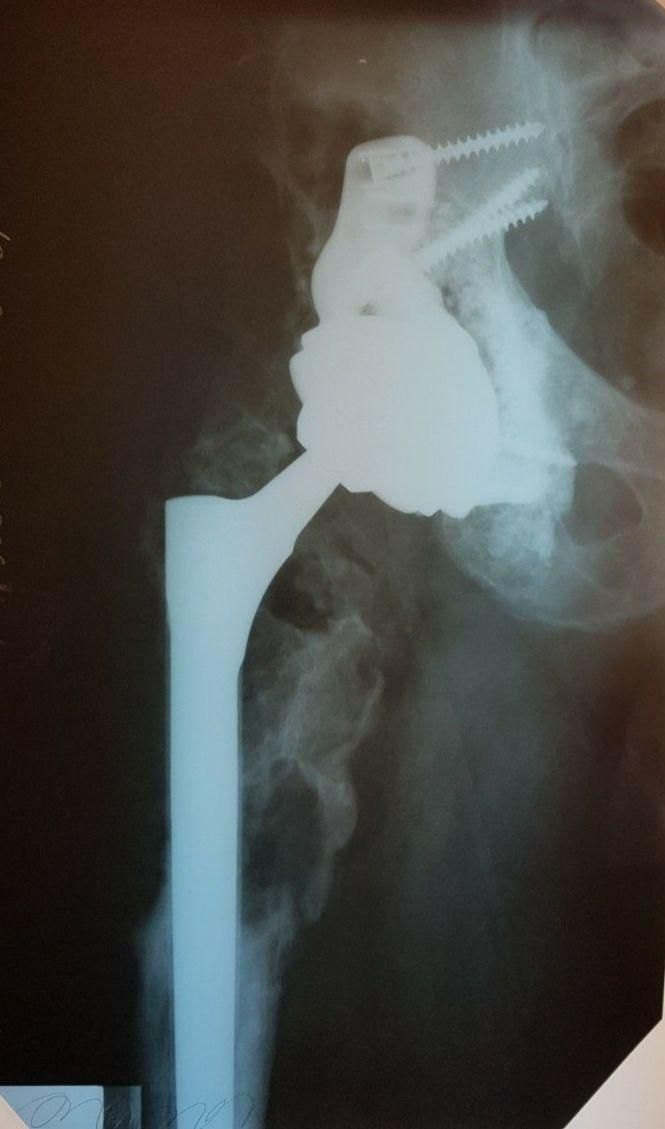

Потенціал точно присутній! Прямі докази тому — діяльність експертів, що взяли участь у згаданих перемовинах. Зокрема, Світлана Валеріївна Бурбурська розповіла про результат унікальної роботи з ендопротезування діафізу стегнової кістки індивідуальним титановим 3D-друкованим імплантатом фермової конструкції в молодої 31-річної пацієнтки з онкодіагнозом, якій прогнозували ампутацію — натомість вона дістала можливість ходити знову. Інтелектуальну частину — проєктування імплантату, індивідуальних навігаційних систем та встановлення — виконали інженери та хірурги Лабораторії в Києві. Безпосередній друк спроєктованої конструкції відбувався у Бельгії. Та вже зовсім скоро весь процес — так би мовити, «під ключ» — будуть реалізовувати в Україні завдяки наявним тут пристроям друку титану та PEEK.